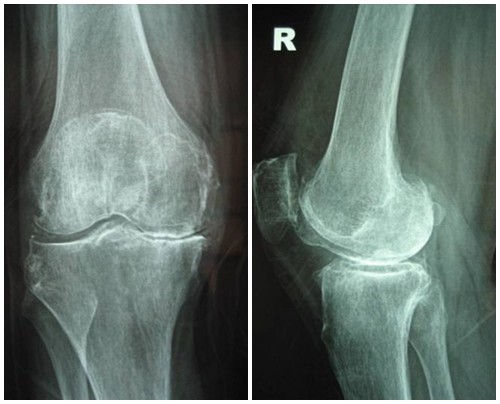

Hình ảnh so sánh giữa khớp bình thường và khớp bị thoái hóa khớp gối

Để phân biệt các giai đoạn của bệnh thoái hóa khớp gối, cần dựa vào phim X- quang theo tiêu chuẩn chẩn đoán thoái hoá khớp của Kellgren và Lawrence như sau:

4. Giai đoạn 4: Thoái hóa khớp gối độ 4

Hình ảnh của khớp gối trên phim X-quang: Khe khớp hẹp nhiều, gai xương có kích thước lớn, đặc xương dưới sụn, đầu xương biến dạng rõ.

Thoái hóa khớp gối giai đoạn 4 là giai đoạn nặng, sụn khớp bị bào mòn

Thoái hóa khớp gối đã bước vào giai đoạn nặng, sụn khớp bị bào mòn và bong tróc gần như hoàn toàn để lộ đầu xương rõ rệt. Khoảng không gian chung giữa hai đầu xương thu hẹp đáng kể, gai xương ngày càng lớn, chất nhờn bôi trơn khớp giảm nên gây ra hiện tượng ma sát giữa hai đầu xương, gây đau nhức xương khớp nghiêm trọng. Người bệnh xuất hiện một loạt các triệu chứng đau nhức liên tục, cứng khớp, khó vận động khớp, khó đi lại… ảnh hưởng đến sinh hoạt. Theo thời gian, thoái hóa khớp gối có thể gây biến dạng khớp hoàn toàn, gây lệch trục khớp…